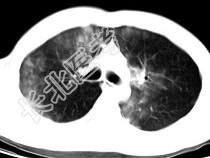

- 单项选择题男,28岁, 外伤后1小时,胸部CT如图, 最可能的诊断为 ( )

A、肺炎

B、肺脓肿

C、肺囊肿

D、肺癌

E、双肺挫伤